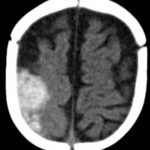

A computed tomography (CT) scan of the head without contrast was obtained out of concern for intracranial pathology due to the patient’s young age and the witnessed focal seizure. The CT showed a 4.2 x 1.2 x 1.5 cm acute extra-axial intracranial right frontoparietal hemorrhage favoring epidural over subdural hemorrhage given its lenticular shape. There was no underlying fracture, herniation or midline shift identified.

Given the concern for non-accidental trauma in this nonmobile child with no history of trauma, pediatric surgery and neurosurgery were consulted and further bloodwork was obtained, revealing elevated partial thromboplastin time (PTT) and a normal prothrombin time (PT). Further work-up led to a diagnosis of severe hemophilia A. He was managed non-operatively with factor VIII infusions to achieve normal factor levels. He remained neurologically stable without further seizure activity during his hospitalization. A skeletal survey showed no fractures. He received levetiracetam for 6 months and had no neurological deficits.